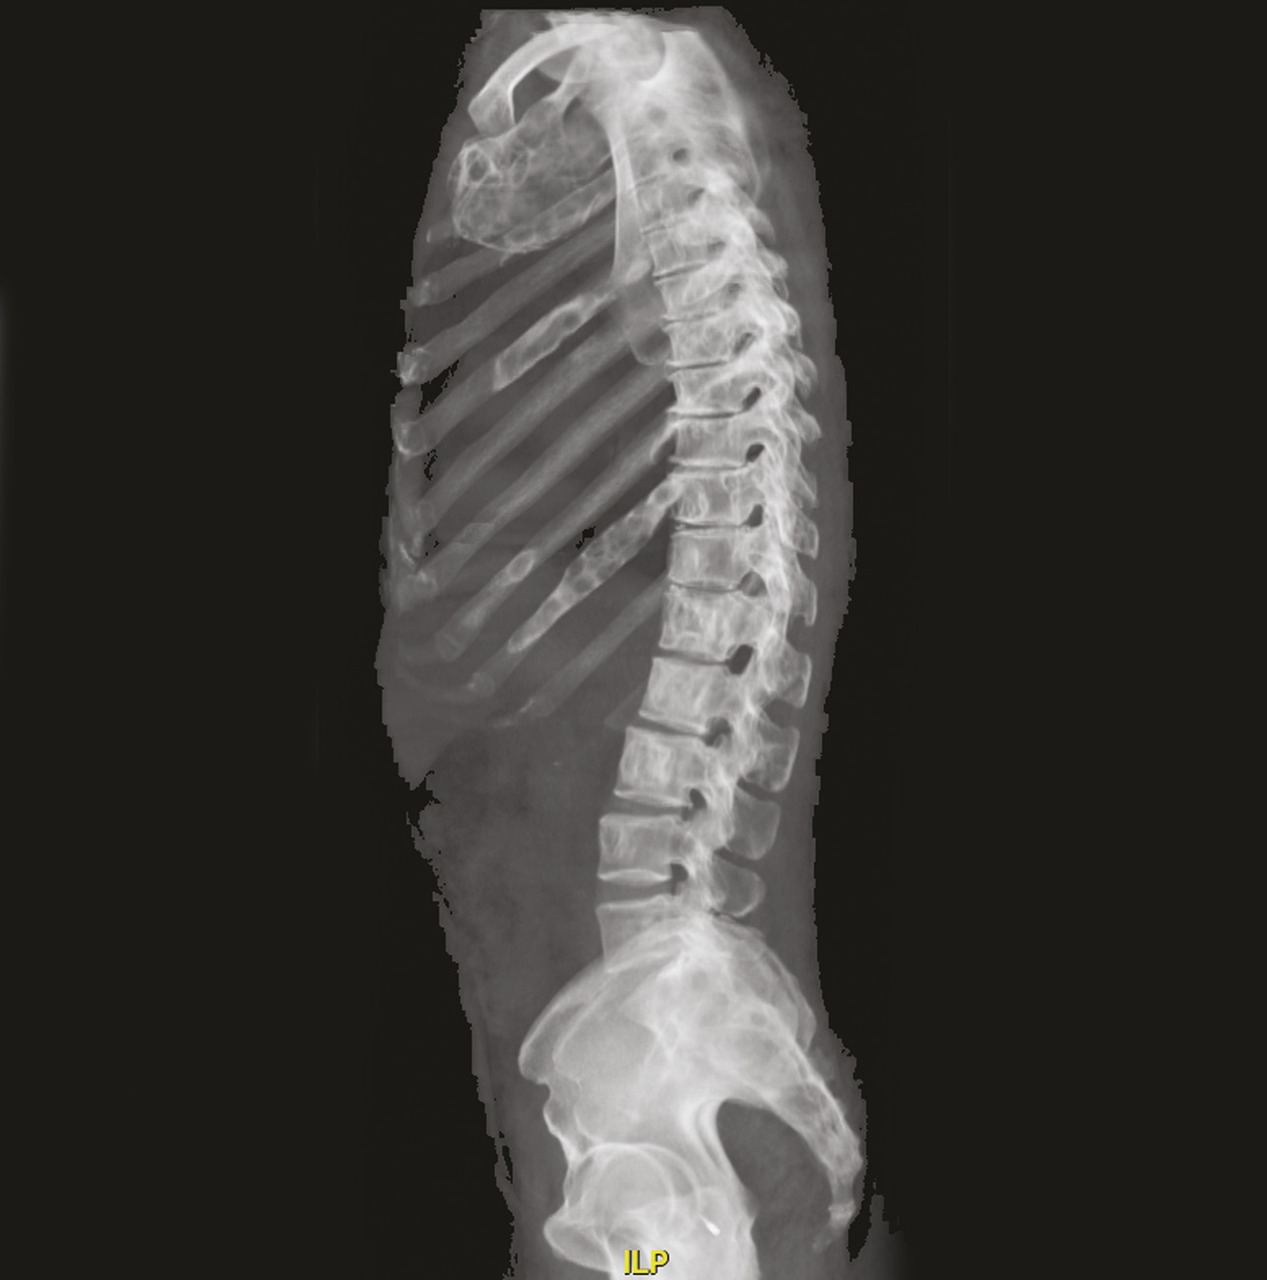

Les images de scanner (fig. 3-5) mettent en évidence de multiples lésions soufflantes avec un aspect en verre dépoli de l’os trabéculaire refoulant la corticale ainsi qu’une érosion marquée de la corticale, sans réaction périostée, confirmant une dysplasie fibreuse polyostotique prédominant au niveau des côtes et du rachis, sans sténose canalaire.